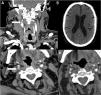

Paciente 8. A. Reconstrucción coronal de angio-TC, con un trombo endoluminal sobre placa de ateroma (flecha blanca) en la Arteria Carótida Interna Derecha (ACI). B. TAC de cráneo sin contraste, con signos de infarto cerebral en el territorio de la ACM derecha. C. angio-TC axial, trombosis aguda en ACI Derecha (flecha blanca). D. Estudio de control pasadas 4 semanas: Angio-TC axial, signos de resolución del trombo endoluminal, la placa de ateroma subyacente determinaba una estenosis residual del 30%.

Paciente 13. A) Angio-TC axial, trombosis endoluminal sobre placa de ateroma en el arco aórtico ascendente. B) Reconstrucción coronal angio-TC. C) Radiografía de tórax, infiltrado bilateral difuso en lóbulos pulmonares inferiores y atelectasias laminares en el lóbulo inferior. D) Reconstrucción sagital de angio-TC de la trombosis endoluminal sobre placa de ateroma en el arco aórtico.